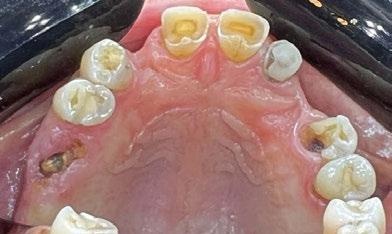

Exploración Intraoral

Presenta un estado oral deficitario. Parcialmente edéntula, con colapso de mordida, migración dental patológica, restauraciones de resina antiguas fisuradas y filtradas, transparencia y exposición de cámara pulpar secundaria a desgastes con pérdida de estructura e integridad de tejido dental importante (Figuras 1 a 4). Portadora a tiempo parcial de prótesis removibles desadaptadas de más de 10 años de antigüedad, refiriendo incapacidad de adaptación a este tipo de prótesis.

Figura 3. Visión intraoral oclusal mandibular. Figura 4. Visión intraoral frontal. Figura 1. Visión intraoral oclusal maxilar. Figura 2. Visión lateral izquierda intraoral. Figura 7. Escaneado intraoral maxilar con Dexis IS3700. Figura 8. Escaneado intraoral mandibular con Dexis IS3700. Figura 5. Visión extraoral lateral sonrisa.